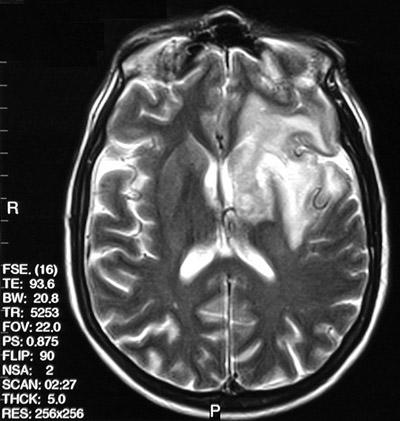

![]() | The axial T2 weighted FSE MRI scan above and the FLAIR MRI scan below both demonstrate an area of enhancement involving primarily the left frontal white matter. There was also extension to basal ganglia, thalamus, and portions of the temporal and parietal lobes in this case of progressive multifocal leukoencephalopathy (PML). Note the relative sparing of the overlying cortex seen best in the FLAIR scan below. |